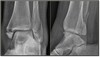

What are the three common types of fractures of the ankle?

1. Pott’s # or Bimalleolar # 2. Trimalleolar # 3. Maisonneuve #

What is the mechanism of injury for a Pott’s # or Bimalleolar #

Caused by forced abduction, eversion, and external rotation

What pathology is present?

Pott’s # or Bimalleolar #

Where is the fracture located in a Pott’s # or Bimalleolar #

Fracture of the medial and lateral malleoli

What part of the ankle is affected in a Trimalleolar #?

Medial, lateral, and posterior malleolus

Trimalleolar #